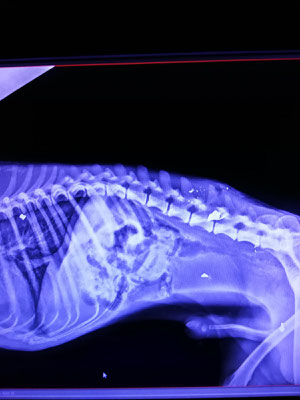

Die Ärzte fanden mehrere Projektile in seinem Körper, das größte im hinteren Bereich der Wirbelsäule. Dieses wurde nach Stabilisierung durch schmerz- und entzündungshemmende Mittel in einer OP entfernt. Bei einem späteren, weiteren Eingriff sollten die restlichen Kugeln herausoperiert werden. Dafür musste Mak aber erstmal wieder zu Kräften kommen. Die Vermutung, dass Mak sehr wahrscheinlich invalide bleiben würde, lag sehr nah, da er nach der Entlassung aus der Klinik nicht stehen konnte.

Doch ein Wunder geschah: Nach einigen Wochen stand der kleine Kämpfer plötzlich auf– wenn auch nicht lange und nur auf einem Hinterbein! Die Hoffnung bestand, dass Mak mit entsprechender Physiotherapie doch wieder würde laufen können. Leider besteht in Kroatien nicht die Möglichkeit für diese Behandlung, daher suchte die Lesika-Hundehilfe dringend eine Pflege- oder sogar Endstelle in Deutschland, damit alles für Mak getan werden konnte, um wieder vollständig gesund zu werden. Nach erneuter Untersuchung stellte man außerdem fest, dass die restlichen Kugeln mittlerweile von Gewebe fest umschlossen waren, sich in stabiler Lage befanden und die Wundheilung sehr gut voran kam. Somit war die geplante, sicherlich nicht ganz ungefährliche, zweite OP Gott sei Dank nicht mehr notwendig.

In seiner Pflegestelle in Deutschland wurde sich dann seit Mitte Oktober letzten Jahres liebevoll um ihn gekümmert und mit physiotherapeutischen Übungen am Muskelaufbau gearbeitet. Bei seiner jetzigen neurologischen Untersuchung zeigte sich eine leichte Arthrose-Entstehung an den Vorderbeinen, die jedoch noch keine Probleme macht. Es wird jetzt angedacht, ihm auf jeden Fall einen angepassten Rolli zur muskulären Entlastung im vorderen und hinteren Bereich zur Seite zu stellen. Die Wirbelsäule ist stabil, durch die Benutzung des Rollwagens können sich keine Splitter an der Wirbelsäule verschieben und das Rückenmark schädigen. Zusätzlich soll Kitai weiterhin Physiotherapie bekommen, so dass die hinteren Beine weiter an Stärke gewinnen und ihm mehr Kraft verleihen.